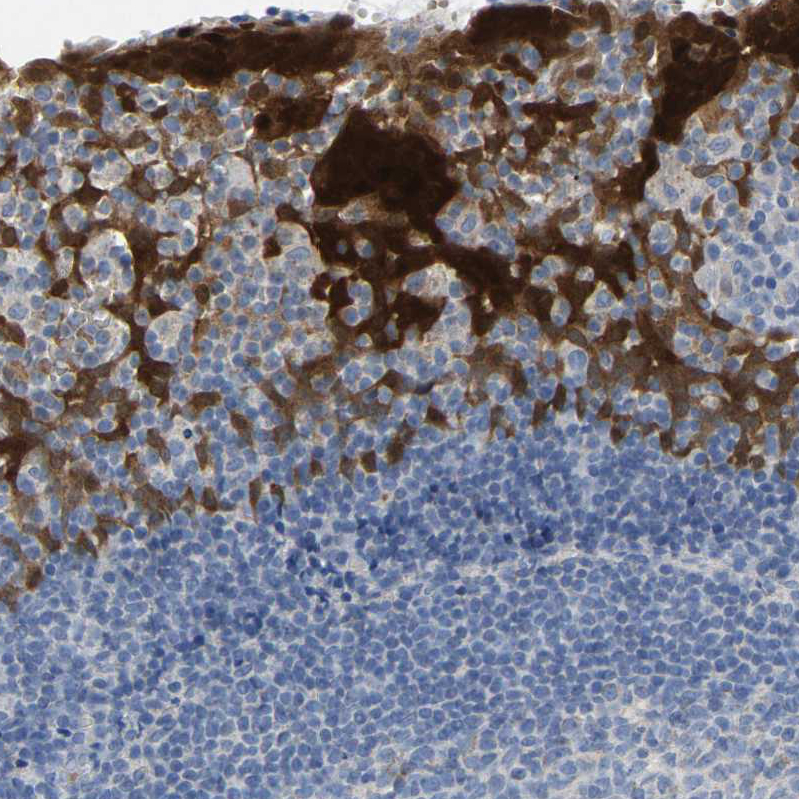

Immunohistochemistry analysis in human skin and skeletal muscle tissues using HPA019025 antibody. Corresponding SERPINB5 RNA-seq data are presented for the same tissues.